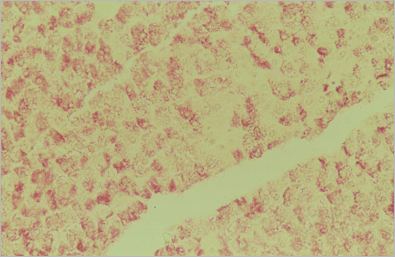

Déchirure (diapo 4)